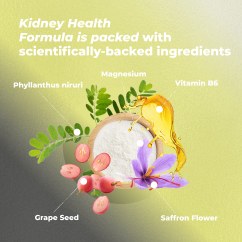

INGREDIENTS:

Vitamin B6

Magnesium

Grape Seed Extract

Phyllanthus niruri

Saffron Flower Extract

Ingredients in Doctor-Approved PureHealth Research Kidney Health Formula are scientifically proven to help:

- MINIMIZE oxidative stress

- REDUCE kidney structure inflammation

- PROMOTE better kidney blood flow

- LOWER protein concentration in the urine

- INHIBIT kidney stone formation

- MAINTAIN stable blood force

- ENHANCE kidney cell repair

- LOWER calcification within the kidneys

- DECREASE the presence of blood in the urine

- NORMALIZE urinary uric acid concentration

- LOWER the number of existing kidney stones